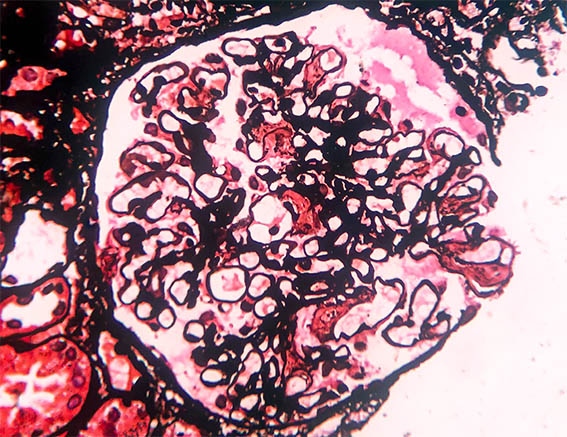

Figure 7. Methenamine-silver stain, X400.

A 53-year-old patient diagnosed with HIV infection 2 years earlier, on antiretroviral treatment, is evaluated for 2 weeks of edema, with no other symptoms. In laboratory tests, the hemoleukogram is normal. CD4 count: 510 /mm2; viral load: less than 500 copies / mL. Nephrotic syndrome was documented, with proteinuria of 7.5 g/24h, hypoalbuminemia, and dyslipidemia. Serum creatinine: 1.0 mg/dL, BUN: 14.0 mg/dL. Studies for hepatitis virus: negative. ANAs and anti-DNA negative; normal serum complement; Non-reactive VDRL. Serum protein electrophoresis: normal.

Renal biopsy is done, look at the images.